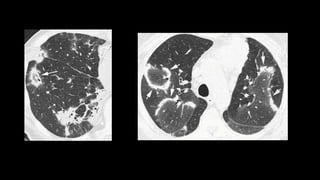

• In early stages, the only HRCT abnormality may be fine reticulation

• Honey combing 3mm to 2 cm, 3 in a row

• reticular opacities

• traction bronchiectasis

• subpleural and lower lobe predominance

• GGOs are rare